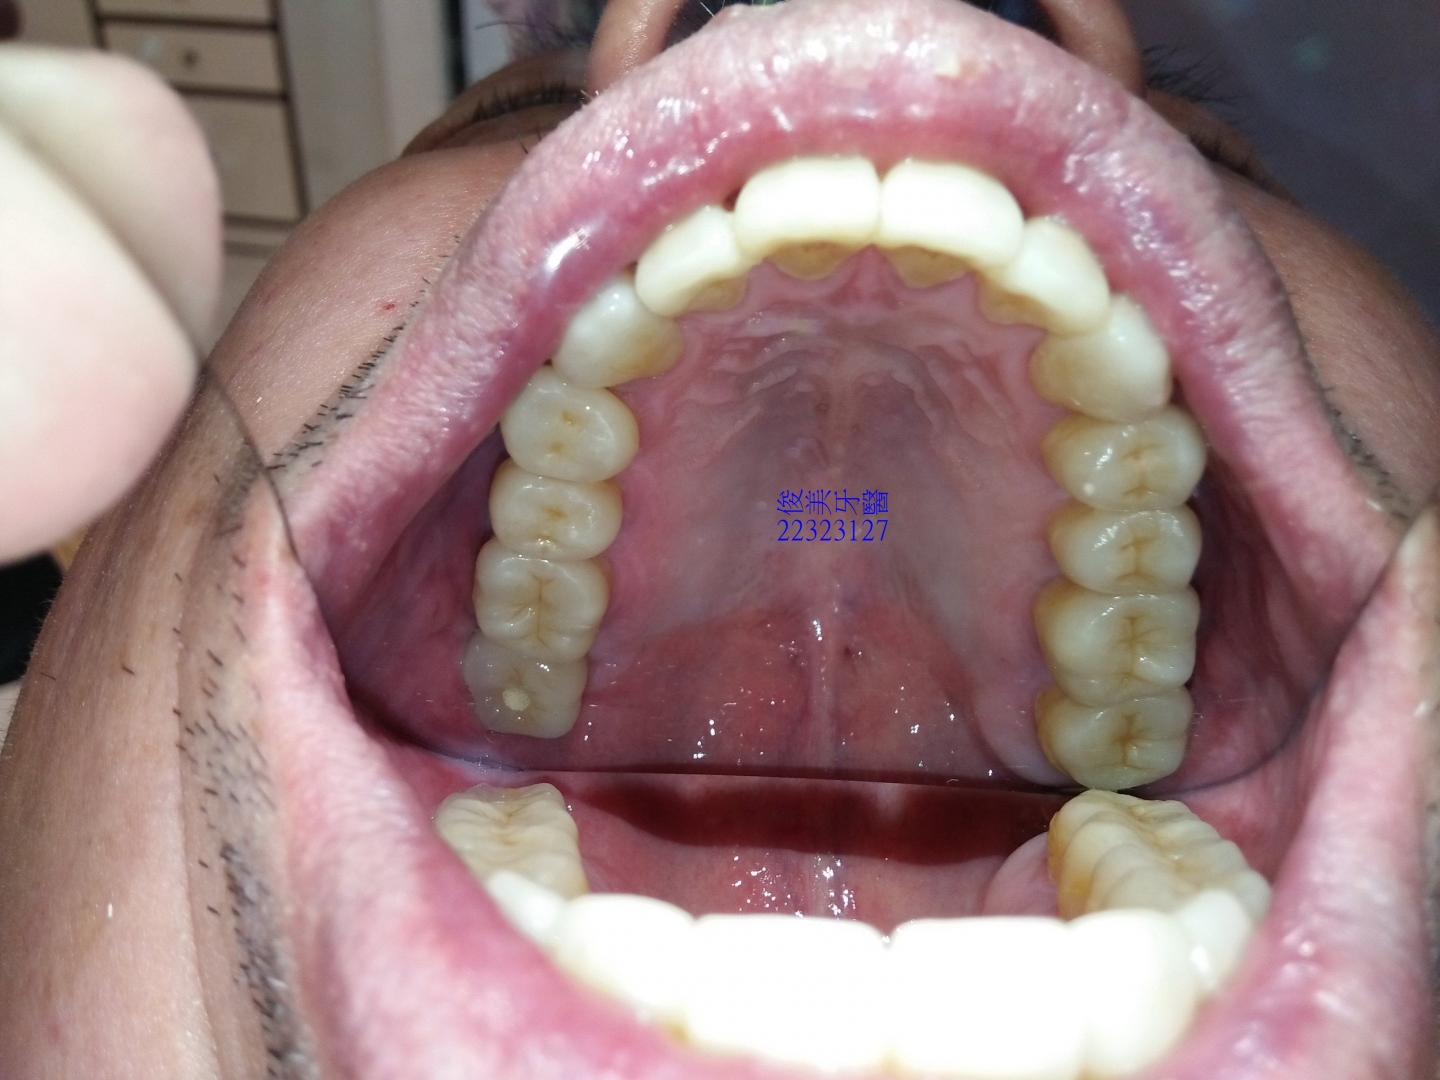

上顎原始狀況。